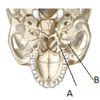

Identify the structures labelled A and B

A- Medial pterygoid plate

B- Lateral pterygoid plate